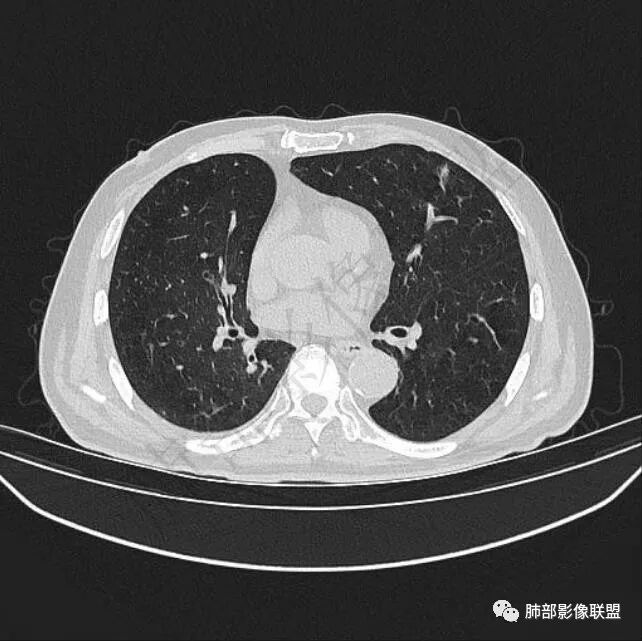

再1个多月后病灶继续增大,较明显不均匀强化,肺门一侧见低密度区。病灶边缘相对不清,可见毛刺。

三.病程脉络相当清楚,即病灶进行性增大,易想到新生物或转移瘤,但经验上分析增长速度显然太快,尤其是对于原发肺腺癌或者肺鳞癌而言,单发转移瘤也较少这样的进展速度。

四.单就影像而言,病灶肿瘤特征不够充分,恶性肿瘤病史,隐球菌等特殊感染确实不能排除。

五.尽管本例鳞癌的病例意见出乎预料,但部分低分化肿瘤迅速增长也不时出现,仍须警惕!